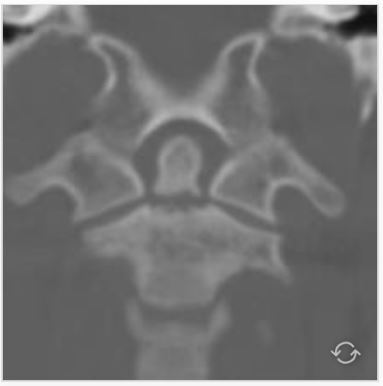

10

what is this and what is it called?

A

burst # of the atlas

Jefferson #